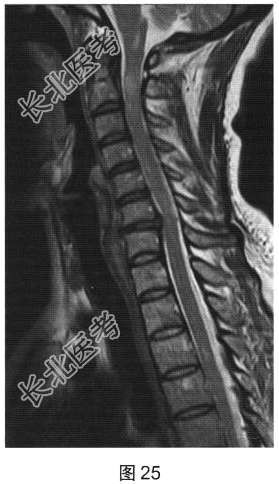

- 简答题2、[提示]患者行脊柱MRI平扫及增强检查,如图25、图26所示。关于MRI检查结果,请描述一下。

- 简答题3、根据脊髓和颅脑MRI表现,病变应诊断为?